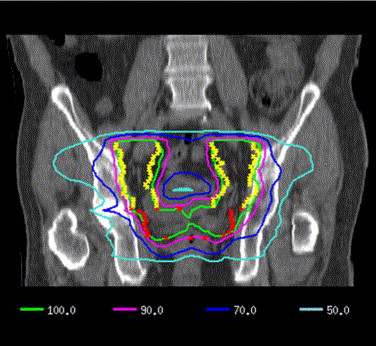

Whole-Pelvis Radiotherapy for High-Risk PCa

When considering treatment with radiotherapy (RT) the patient and treating physician often have to engage in a balancing act. RT can certainly destroy cancerous tissue, but it may also damage healthy tissue which can result in subsequent quality of life issues for the patient. The radiation oncologist wants to ensure that the cancer cells receive enough radiation to kill them, but at the same time to spare as much healthy tissue as possible from the harmful radiation.

Prostate cancer cells can make their way to lymph nodes in the pelvic area and will need to be irradiated if the RT is to be successful. The issue is posed in this study as reported to the European Society for Radiation Oncology (ESTRO) at last year’s virtual meeting. The study sought to determine if more extensive radiation of the pelvic region, including the lymph nodes, would be of benefit to prostate cancer patients having RT. According to the results of this randomised controlled trial, irradiating the whole pelvis rather than just the prostate reduces the likelihood of recurrence in men with high-risk locally advanced prostate cancer (PCa). Results from the trial, called POP-RT, were reported at the 2020 European Society for Radiology and Oncology (ESTRO) Online Congress.